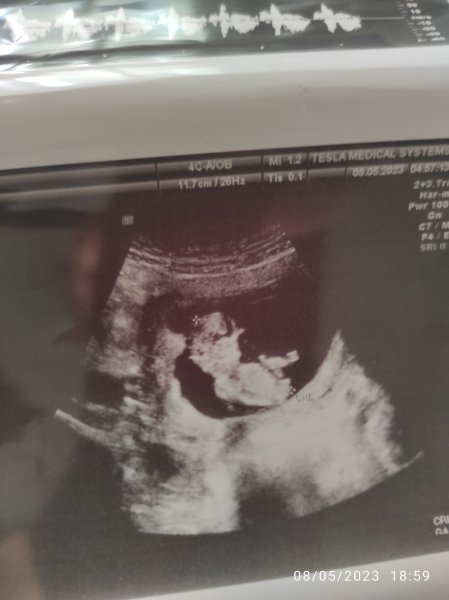

Canım. Benim bebiseme de bakar mısın 12+1Selamlar, Ultrason sonucuna göre cinsiyet tahmini var tabiki NUB TEORİSİNE GÖRE CİNSİYET başlıklı konumuzdan resimleri nasıl atacağınız ifade edilmiştir. Hemen konuda aşağıda yer alan özellikle cinsiyet belirlemede olması gereken çıkıntıların çıktısının olması gerekiyor. Bu resimlerin büyüğü var ise gönderin bize ya da linkini verdiğimiz konuya bakarak kendiniz de tahminde bulunabilirsiniz.

Vallahi ben uzman değilim ve Gaybı geleceği olacağı ancak Allah bilir ha illa yüzde verin diyor iseniz %52 kız diyelim![]()